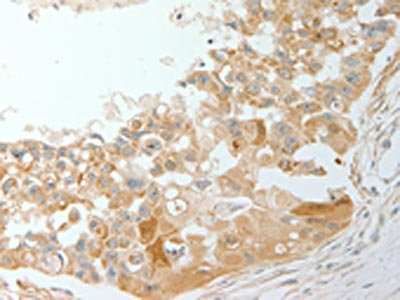

The image on the left is immunohistochemistry of paraffin-embedded Human breast cancer tissue using CSB-PA889716(ADM Antibody) at dilution 1/20, on the right is treated with synthetic peptide. (Original magnification: ×200)

The image on the left is immunohistochemistry of paraffin-embedded Human cervical cancer tissue using CSB-PA889716(ADM Antibody) at dilution 1/20, on the right is treated with synthetic peptide. (Original magnification: ×200)